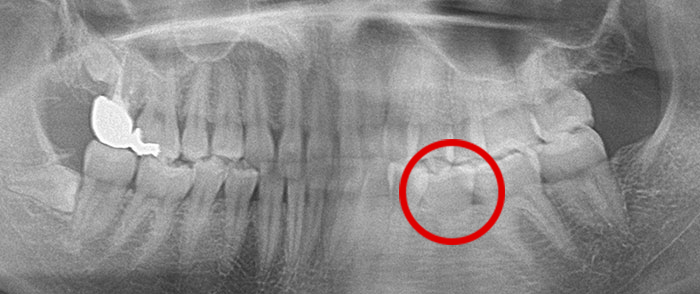

真横になった親知らずを抜歯したレントゲン写真です。